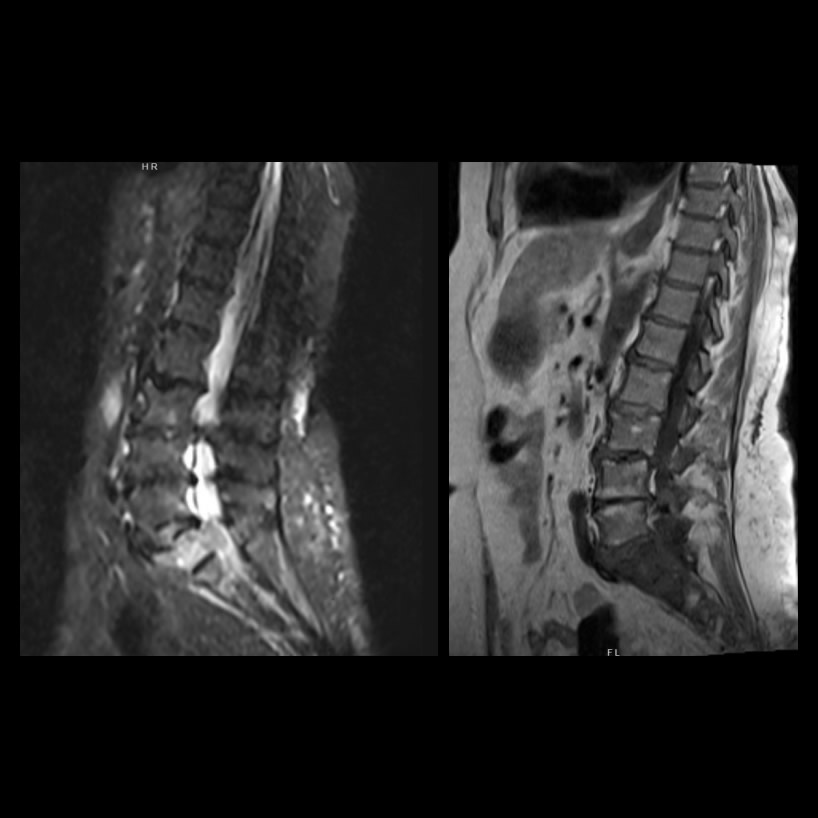

Mujer de 76 años con dolor lumbar y claudicación intermitente